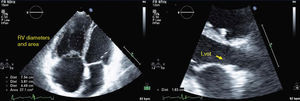

other parameters for characterization of RV morphology and function: in apical 4-chamber view, diastolic RV diameters (Figure 1) and the gradient between the right ventricle and right atrium in systole (RV/RA gradient). In parasternal short-axis (at the level of the papillary muscles): left ventricular diastolic diameters, to calculate the diastolic left ventricular eccentricity index (LVEI) (Figure 3).

Figure 3.Echocardiographic measurements in a pulmonary hypertension patient at rest (left) and at peak exercise (right); top – diastolic left ventricular eccentricity index; bottom – RV/RA gradient. D1 and D2: left ventricular diameters; LV exc index: diastolic left ventricular eccentricity index; RV/RA grad: right ventricular/right atrial gradient in systole.